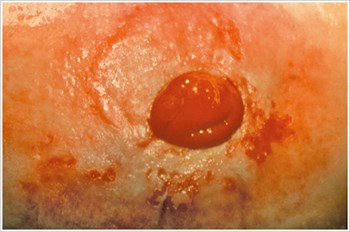

Tlakový vred

Popis/príčiny:

Vred v peristomálnej oblasti spôsobený nadmerným tlakom zo stomického systému, tesného oblečenia, perastomálnej hernie alebo pracovných návykov.

Symptómy:

- Bolesť

- Vred nepravidelného tvaru

- Podtekanie pod pomôcku

- Znížená doba nosenia